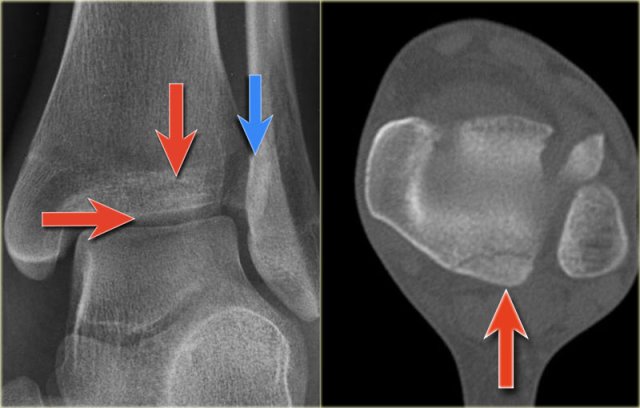

Study the images and then scroll to the next images.

The fracture through the epiphysis can be easily missed (blue arrow).

The fracture through the growth plate is only seen on CT.

Continue with the CT images.

The CT-images nicely display the fracture through the growth plate and the epiphysis.